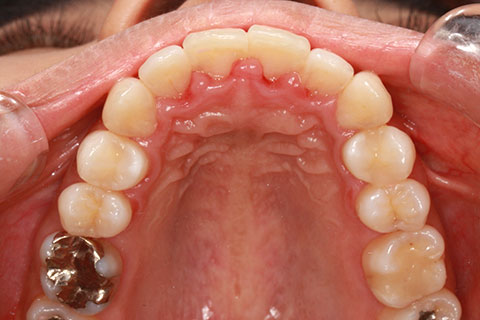

ハーフリンガル矯正3:上の歯のみ舌側矯正で治療(矯正期間24ヶ月)

治療前

治療中(開始直後)

治療中(開始半年後)

治療後

- 年齢・性別

- 25歳女性

- 治療期間

- 2年0ヶ月

- 抜歯

- 上下4番抜歯

- 治療費

- 110万円

- 治療内容

- 施術の副作用(リスク)

- 表側矯正と比較して、力学的な操作性が複雑なため、ボーイングエフェクトを起こしやすい。